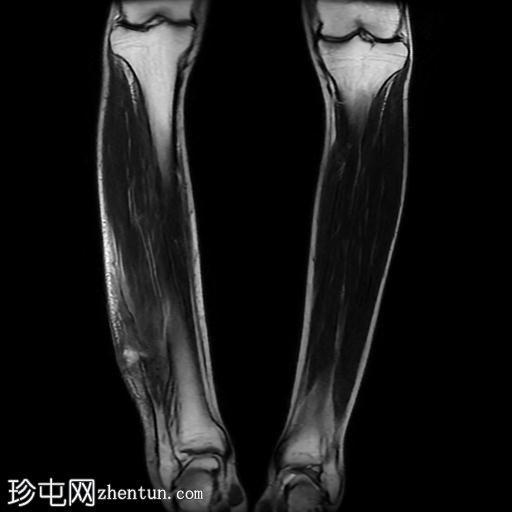

冠状位

T2加权像

3.jpg

腓骨可见广泛的骨髓水肿,伴有明显的皮质和骨膜增厚,整个腓骨均呈高信号。腓骨外侧中下三分之一交界处可见局灶性皮质破坏,并可见一条高信号瘘管延伸至周围皮肤。

此外,软组织(包括肌肉和皮下组织)也受累。

腓骨弥漫性骨髓信号异常,伴有明显的皮质和骨膜增厚,窦道自腓骨延伸至皮下区域。MRI 影像学表现符合腓骨骨髓炎。